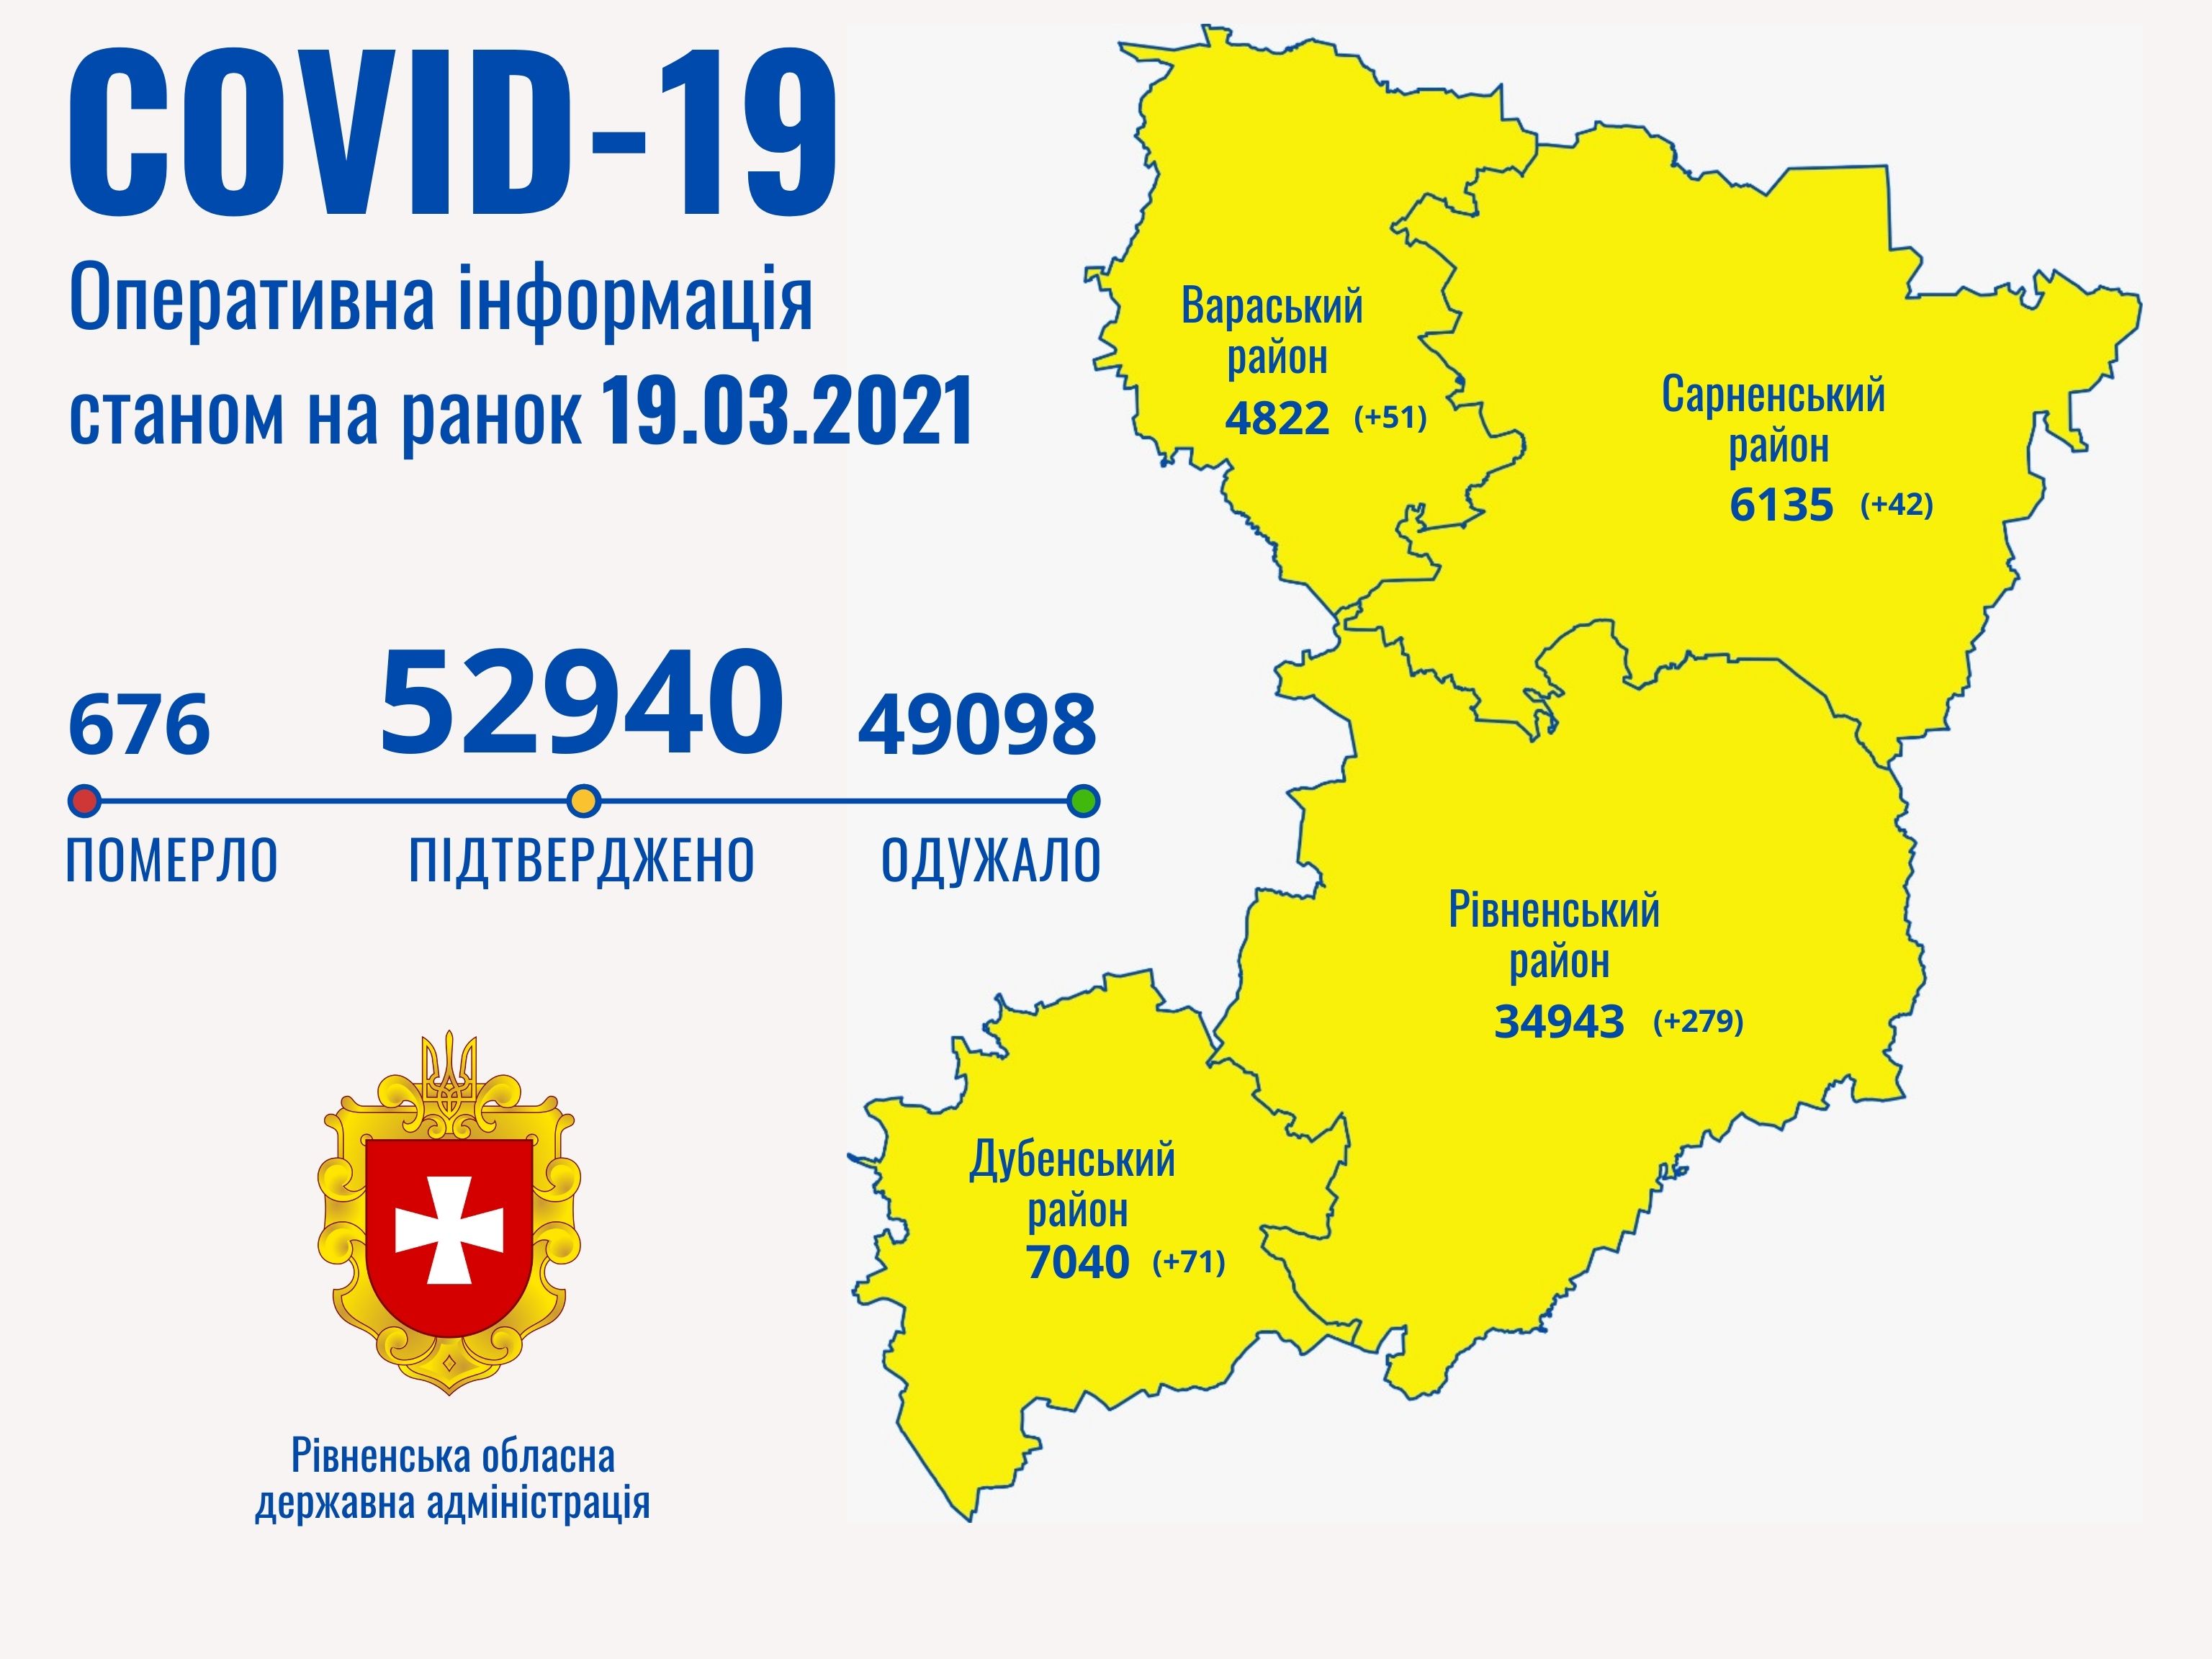

Коронавірус повертається: як стрімко зростає кількість хворих на Рівненщині (ВІДЕО)

Пів тисячі - у важкому стані, 9 жителів Рівненщини померли за добу від коронавірусу